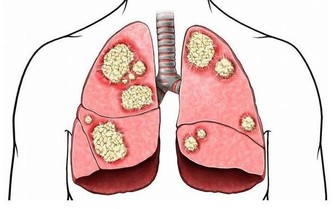

事實上,脂肪肝會導致更嚴重並且常常是致命的肝臟疾病,包括肝癌。肝病的主要階段包括單純性脂肪肝(脂肪變性)、纖維化和最嚴重的階段,也就是肝硬化,它可以導致肝功能衰竭和肝癌。

然而,當病情變得更加嚴重時,會導致腹痛、疲勞、極度疲倦、不明原因的體重減輕和虛弱。如果肝硬化發展,患者可能出現嚴重症狀,比如皮膚和眼白色變黃,腿部、腳踝、腳或肚子腫脹。然而等到那時候,就已經太晚了。